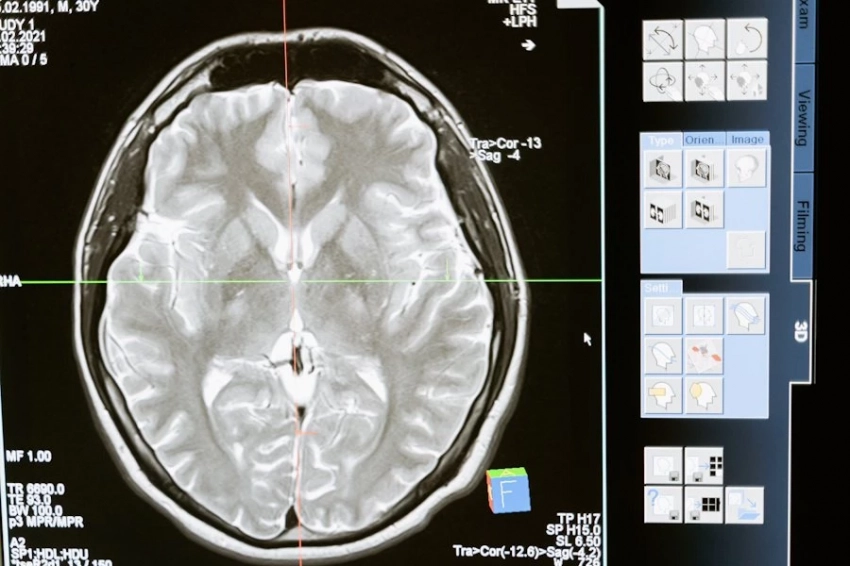

Одно из самых обсуждаемых открытий последних лет принадлежит канадским исследователям. Во время электроэнцефалографии у 87-летнего пациента, умершего прямо во время процедуры, ученые зафиксировали, что мозг продолжал проявлять активность еще в течение 30 секунд после остановки сердца. Более того, эта активность напоминала мозговые волны, характерные для сна или глубокой медитации.

Еще один важный аспект — гипоксия, то есть нехватка кислорода, которая наступает практически сразу после остановки сердца. Именно это состояние, по мнению ученых, может вызывать характерные для околосмертного опыта галлюцинации: свет в конце тоннеля, парение над телом, встречи с умершими родственниками.

Многие люди, побывавшие в состоянии клинической смерти, описывают свои переживания схожим образом. Исследователи считают, что в данном случае речь идет не о мистике, а о реакции мозга на экстремальные условия. Однако и это пока только гипотеза — прямых доказательств нет, сообщает echonedeli.ru.